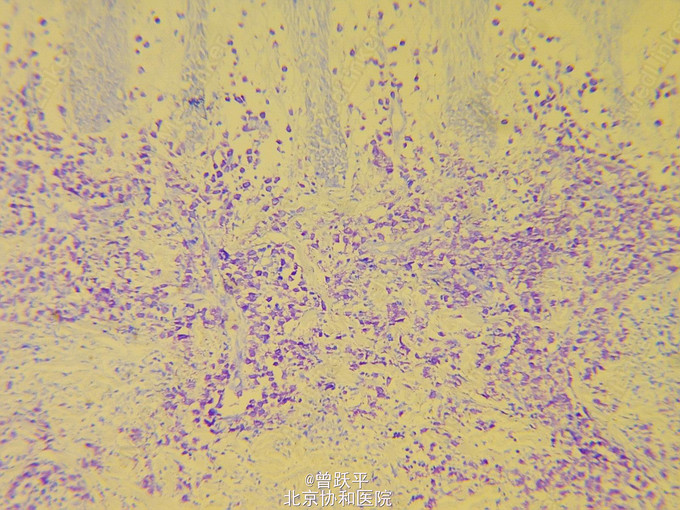

患儿女,5个半月。 因右手背皮肤结节、水疱、血疱,伴全身反复出现红斑、风团5个半月来我院就诊。 患儿出生时,右手小指掌指关节伸侧有一绿豆大丘疹,摩擦后肿大,表面起水疱、大疱或血疱,皮损渐增大。 患儿常出现全身阵发性红斑、风团和面色苍白,持续约数小时至数天后缓慢消退。 个人史:患儿系第一胎第一产,足月顺产。 家族中无类似患者。

查体:一般情况良好。系统检查无异常。全身浅表淋巴结未触及。 右手小指掌指关节伸侧可见一1.4cm×2.5cm棕红色结节,界清,橡皮样硬度。 躯干、四肢散在分布许多大小和形态不一的红斑和风团

单发性肥大细胞瘤 口服氯苯那敏2mg/d,红斑和风团明显减少,此后右手背皮损逐渐变小。